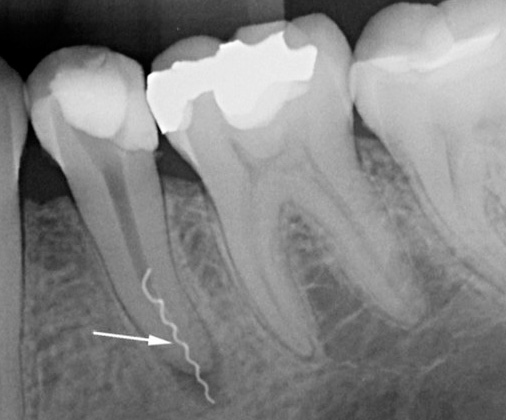

Le violazioni gravi del medico sono:

- riempimento di scarsa qualità del canale o dei canali;

- rottura dell'utensile nel canale;

- creando perforazioni nel canale (fori o danni alla parete della radice).

Se nel trattamento della pulpite cronica o delle sue esacerbazioni c'è un riempimento incompleto dei canali o il loro riempimento eccessivo (rimozione del materiale all'apice), immediatamente o dopo un po '(da un giorno a un anno o più) compaiono sintomi corrispondenti alla periodontite nell'esacerbazione. In questo caso, possono esserci spesso dolori acuti, l'incapacità di toccare il dente anche con la lingua, la natura pulsante del dolore e in alcuni casi, dopo qualche tempo, possono verificarsi gonfiore della mucosa nella regione dell'apice della radice del dente.

Quando uno strumento viene rotto nel canale, il dente potrebbe non manifestarsi a lungo, ma prima o poi l'infezione nella sezione della radice "non pulita" e non sigillata causerà un processo purulento nel canale con la formazione di un "flusso", o il processo avrà una forma cronica con formazione al meglio fistole (dotti che si aprono sulle gengive, attraverso le quali il pus dalla radice del dente viene secreto nella cavità orale) e, nel peggiore dei casi, la formazione di sacche purulente - cisti.